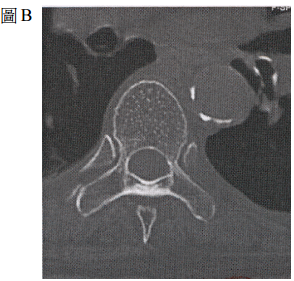

75 75 歲女性病患,背部疼痛多年,最近 3 個月加劇,經影像檢查除了主動脈鈣化明顯外,腰椎及椎體 也有變化;圖 A 為腰椎側面 X 光攝影,圖 B 為電腦斷層掃描之橫切面。這位病患最可能的診斷為何?

(A) 感染性脊椎炎 (B)癌細胞骨轉移及病理性之壓迫性骨折 (C)骨質疏鬆症之壓迫性骨折 (D)外傷性壓迫性骨折